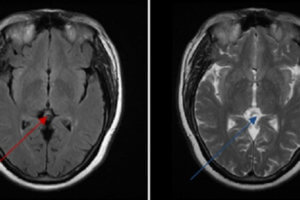

Wilson’s Disease

Wilson disease is an autosomal recessive disorder of copper metabolism. Patients with the disease experience excessive deposition of copper in the liver, brain, and other tissues. It appears that the primary defect... Read more »